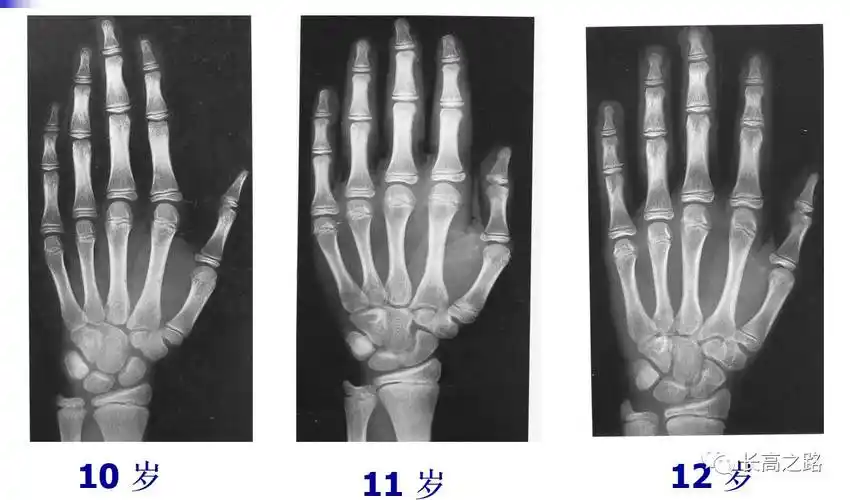

骨龄几岁还能长高吗女孩篇

骨龄图

收藏丨骨龄图谱!(方便随时对照)

教你简单识别孩子的骨龄片

收藏丨骨龄图谱方便随时对照